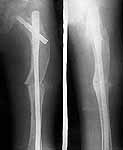

I did not have Zickel nail so planned for Gamma. Had to open the fracture site as could not reduce it closed. Also did a wedge osteotomy in mid shaft level to correct the deformity. The wide canal diameter allowed me to pass the straight nail down the canal. The thigh is now straight, leg length almost equal ( affected leg is probably 1/2 cm longer !) and no neurovascular deficit.

The patient is delighted and working hard on knee flexion and has acheived up to 90 degrees now. Histopathology has come back as fibrous dysplasia. I am attaching the pre op and post op xrays.

preop

postop